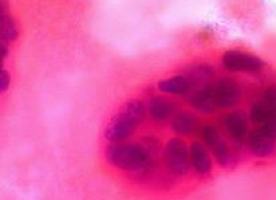

An independent panel of experts has concluded that routine breast cancer screening results in a reduced risk of dying from breast cancer compared to when no screening takes place, but that screening also results in overdiagnosis, according to a Review published in The Lancet.

When breast cancer is detected by screening, it generally allows for earlier treatment and an improved prognosis for the patient.

However, concerns have recently been raised about overdiagnosis – where screening identifies a tumour, which is consequently treated by surgery, and often radiotherapy and medication, but which would have remained undetected for the rest of the woman’s life without causing illness if it had not been detected by screening.